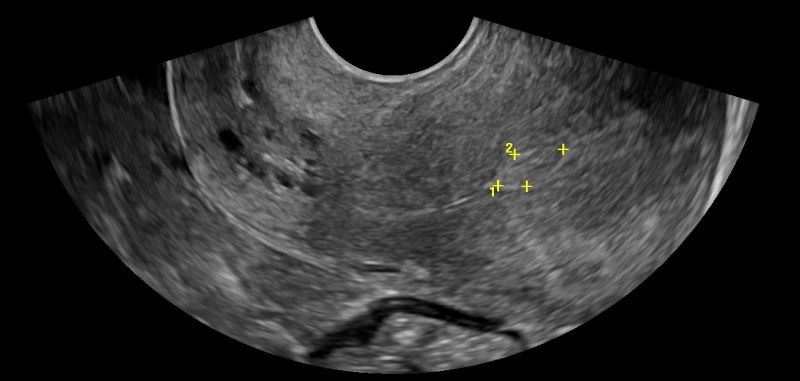

- Ωοθήκες: Η απεικόνιση των ωοθηκών περιλαμβάνει την αξιολόγηση του μεγέθους, της μορφολογίας και της υφής τους. Με το Διακολπικό Υπερηχογράφημα, μπορούν να μετρηθούν τα ωοθυλάκια και να διερευνηθεί η παρουσία συνδρόμου πολυκυστικών ωοθηκών. Οι εστιακές βλάβες στις ωοθήκες, συμπαγείς ή κυστικές, μπορούν να αξιολογηθούν ως καλοήθεις ή ύποπτες, με τη βοήθεια του Έγχρωμου Doppler για την απεικόνιση της αγγείωσης και της ροής του αίματος.